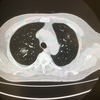

胸部CTでは右肺上葉に40mm大の腫瘤を認め、その末梢側にも淡い陰影が広がっていました。